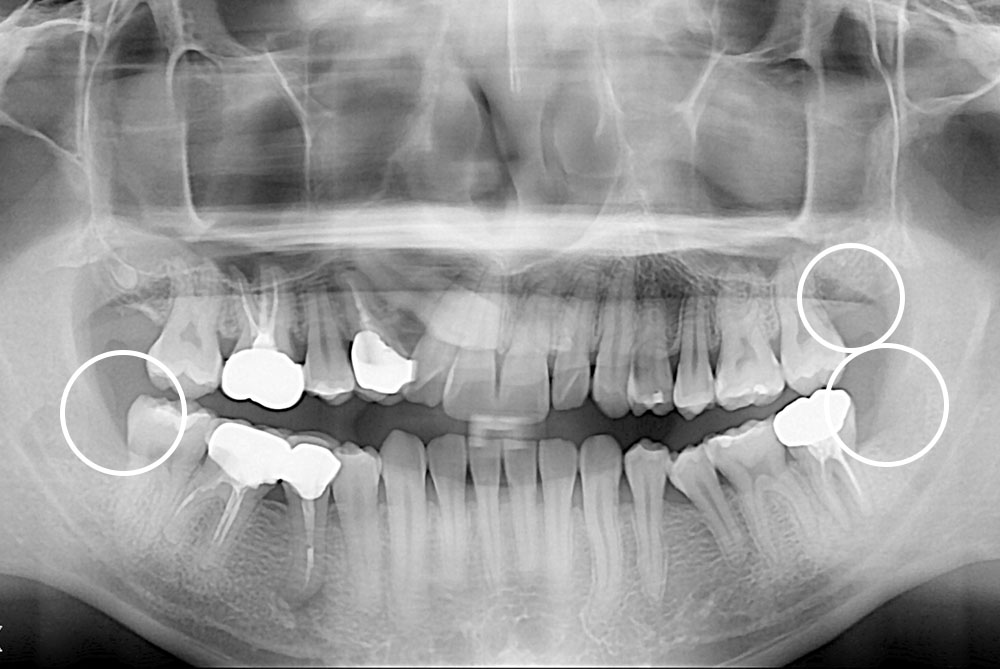

[사랑니] 매복 사랑니 발치

치료전 : 2018-08-27